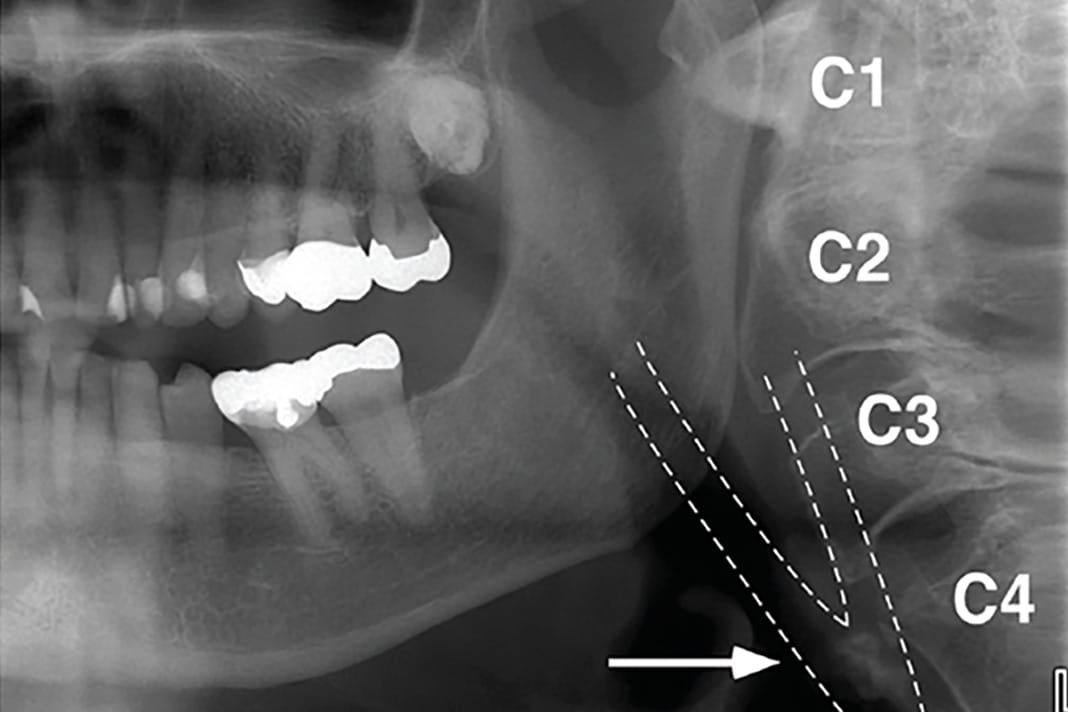

On a PAN, carotid artery calcification (CAC) can appear as a radiopaque lesion that is either rounded or nodular in shape (see Images 1 and 2).9,10 CACs most often present themselves between the C3 and C4 vertebrae. They can be localized to one side or appear bilaterally.10 Moshfeghi et al. stated, “Panoramic radiographs may help us to detect CACs in patients with or without other associated risk factors.”10 This means dental hygienists may be the first ones to discover these in their patients.

In these images, CACs most commonly appear in the cervical tissue. From the axial view, they can be described as “single or multiple “rice grains” with a homogeneous opacity and a linear or curvilinear shape.” They appear “approximately 0 to 10 mm anterolaterally to the anterior tubercle of the transverse process; lateral or more often lateroposterior to the greater cornu of the hyoid bone; and always posterolateral to the pharyngeal airway space. In coronal projections, CAC depiction appears lateral to the anterior tubercle of the cervical vertebrae. On the sagittal sections, CACs are identified medial and inferior to the angle of the mandible, lateral and mostly anterior to the cervical tubercle with their vertical position varying from C3 to C5.”12